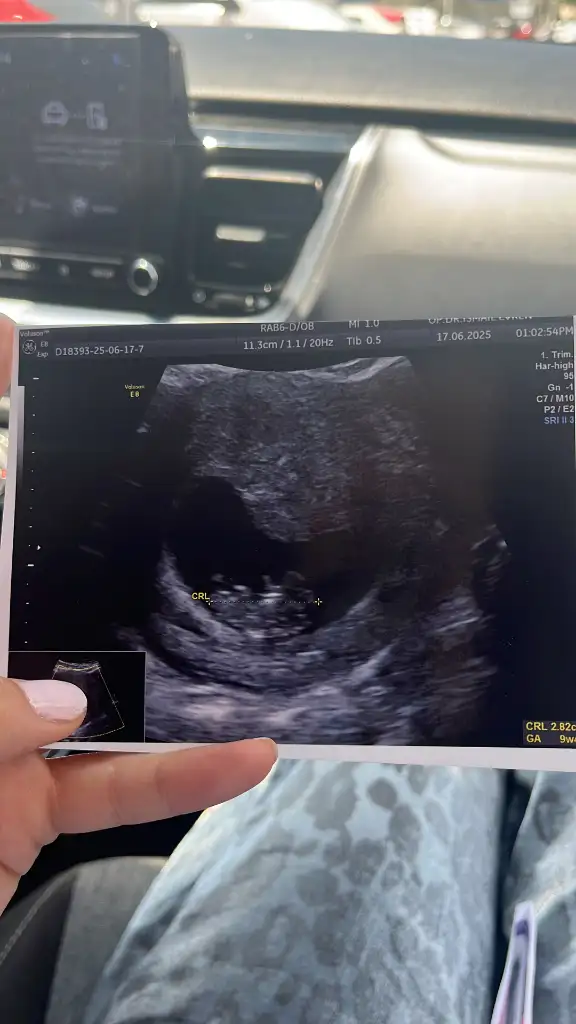

Bana da bakar mısınız lütfen biri 9 haftalık biri 6 haftalık karından ultrasonKese şekline göre erkek bence. Sağlıkla kucağınıza alın

Banada bakar mısnız lütfennnn çok merak ediyorum biri 9 haftalık biri 6 haftalık ultrason karından

Erkek bence. Sağlıkla kucağınıza alınBana da bakar mısınız lütfen biri 9 haftalık biri 6 haftalık karından ultraso

Tahmin edebilirmisiniz rica etsemErkek bence. Sağlıkla kucağınıza alın